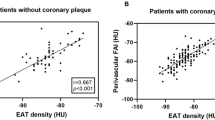

High- and low-EATV groups

With regard to clinical characteristics, there were no significant differences between the two groups in terms of the age, sex, BMI, and prevalence of diabetes (Table 1). Regarding medications, the percentage of patients using statins was significantly larger in the high-EATV group, accounting for 61.5 % of the high-EATV group versus 38.5 % of the low-EATV group. As shown in Table 2, there were no significant differences between the two groups in terms of angiographic characteristics such as the severity of stenosis, lesion length, and lesion distribution. IVUS data are shown in Table 3. No difference was detected between the two groups with respect to the MLA and lumen volume at the lesions. The reference area at the MLA site was larger in the high-EATV group than in the low-EATV group (76.5 ± 8.3 vs 72.9 ± 10.2, P = 0.03), but there was no significant difference in the remodeling index. Also, positive remodeling was more advanced in the high-EATV group (1.08 ± 0.16 vs 0.87 ± 0.14, P = 0.04). Plaque volume at the lesion was larger in the high-EATV group than in the low-EATV group. Furthermore, additional analysis of plaque characteristics revealed significantly higher percentages of lipid, necrotic, and calcified tissues in plaque from the high-EATV group. With regard to fibrous tissue, however, no significant difference was detected between the two groups. Subsequently, we assessed the correlation between EATV and MLA (Fig. 4), the vessel diameter at the MLA site, the plaque volume at the lesion site, and the blood vessel volume, but no significant correlations were found among these factors. We also assessed the correlation between EATV and each plaque component (Fig. 5), revealing a significant negative correlation between EATV and fibrous tissue (R 2 = 0.24, P < 0.01), as well as a significant positive correlation between EATV and necrotic tissue (R 2 = 0.34, P < 0.01). However, lipid tissue and calcified tissue showed no significant correlation with EATV. We also performed multivariate analysis of the variables related to necrotic plaque, which is regarded as vulnerable plaque, employing hemoglobin A1c (HbA1c), low-density lipoprotein (LDL) cholesterol, high-density lipoprotein (HDL) cholesterol, eicosapentaenoic acid/arachidonic acid (EPA/AA) ratio, highly sensitive C-reactive protein, BMI, and smoking status. As a result, LDL cholesterol (β = 0.15, P = 0.03) and EATV (β = 0.14, P = 0.02) were identified as factors predicting plaque with a high percentage of necrotic tissue (Table 4). In addition, we performed multivariate analysis of the variables related to necrotic tissue in high-EATV group. LDL cholesterol (β = 0.10, P = 0.04) was identified as a factor. However, correlation was very weak.

EATV and plaque vulnerability

The relation between EATV and plaque vulnerability has been assessed using CT data in several previous studies [3–5]. IVUS is superior to CT for characterizing coronary plaque, as described above. In addition, performing iMap-IVUS at 40 MHz is a new technique for more objective and reproducible characterization of plaque components at higher resolution [10]. Our study revealed a positive correlation between EATV and components of vulnerable plaque such as necrotic tissue, while there was a negative correlation between EATV and fibrous tissue. Attenuation accompanied by calcified tissue and artifacts from guide wires are sometimes recognized as necrotic tissue when using the iMap system, whereas the QIVUS software defines these as unknown plaque. Because there was only a small difference in calcified tissue between the two groups compared with that of necrotic tissue, the possibility of the study results being influenced by calcified tissue and wire bias can be ruled out.